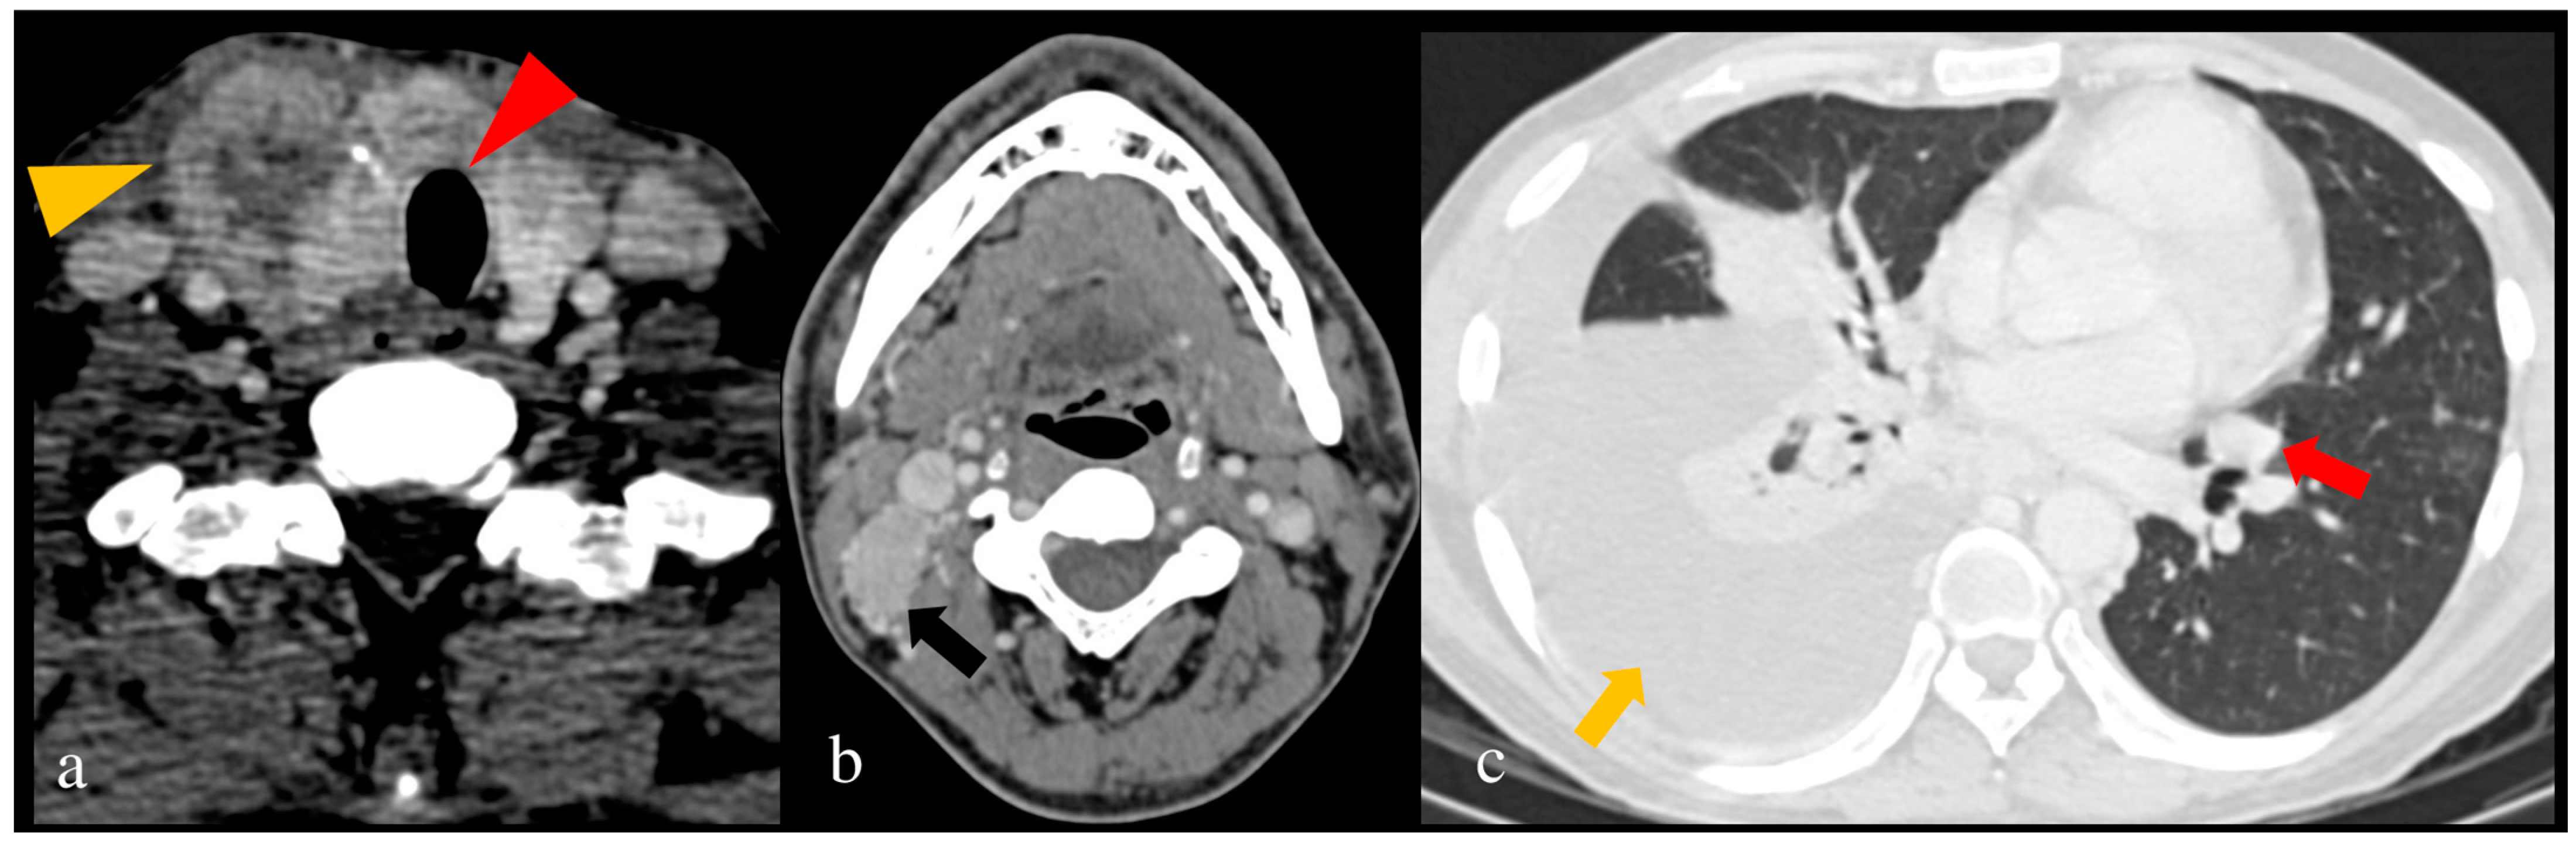

- Vaish, R.; Mahajan, A.; Sable, N.; Dusane, R.; Deshmukh, A.; Bal, M.; D’cruz, A.K. Role of computed tomography in the evaluation of regional metastasis in well-differentiated thyroid cancer. Front. Radiol. 2023, 3, 1243000. [Google Scholar] [CrossRef] [PubMed]

- Mahajan, A.; Vaish, R.; Sable, N.; Arya, S.; Kane, S.V.; D’Cruz, A. 391P Incremental value of preoperative CT in the surgical management of papillary thyroid cancer. Ann. Oncol. 2016, 27, ix121. [Google Scholar] [CrossRef]

- Mahajan, A.; Agarwal, U.; Padashetty, S.; Shukla, S.; Smriti, V.; Rastogi, S.; Vaish, R.; Kumar, S.; D’Cruz, A. A narrative review of the role of cross-sectional imaging in the management of thyroid carcinoma: Imaging guidelines and T-CIRADS. Cancer Res. Stat. Treat. 2022, 5, 490–498. [Google Scholar] [CrossRef]

| Seo et al. (2010) [76] | Diagnostic accuracy for ETE | 84 | CT | For tracheal invasion: S = 59.1%, Sp = 91.4%, A = 83.2% For esophageal invasion: S = 28.6%, Sp = 96.2%, A = 90.7% For invasion of CCA: S = 75.0%, Sp = 99.4%, A = 98.8% For invasion of IJV: S = 33.3%, Sp = 98.8%, A = 97.1% For invasion of RLN: S = 78.2%, Sp = 89.8%, A = 85.5% | Despite a low sensitivity, CT can be a valuable modality for ETE detection. |

| Zhang et al. (2020) [85] | Diagnostic study for PTC | 82 | CT | S = 87.8%, Sp = 94.2%, A = 91.1% | Irregular ring, marginal defects, and enhanced blurring on CT were strongly correlated with PTC. |